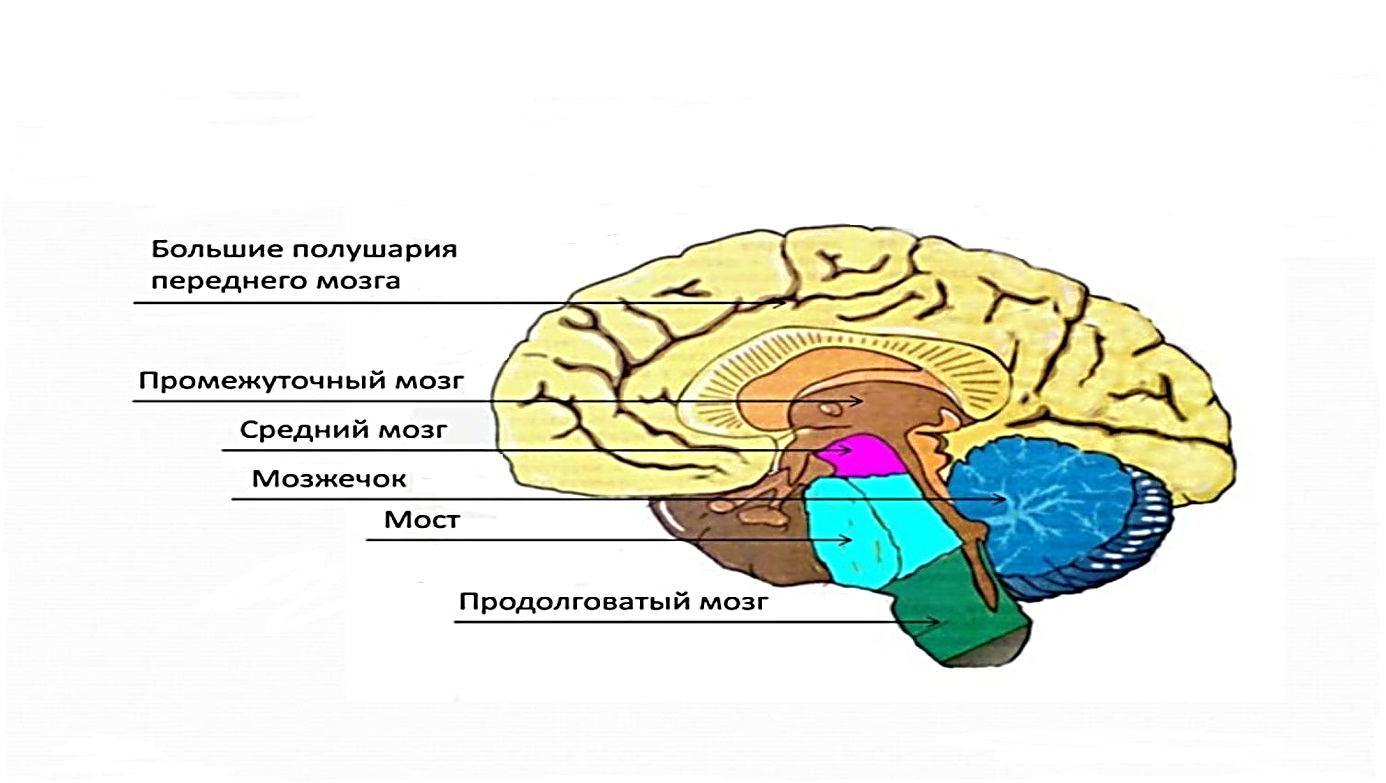

Анатомические снимки верхнелатеральной поверхности головного мозга